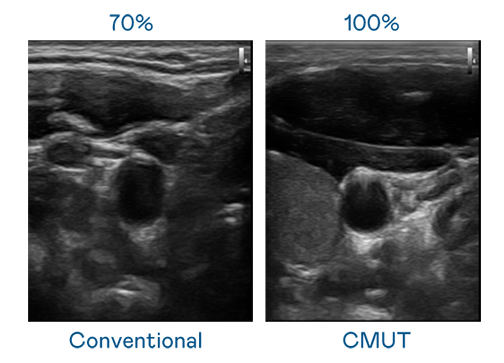

CMUT 技术是一种用电容式微机电元件来产生超音波讯号的技术。与传统 PZT 压电式技术相比,CMUT 频宽增加 30%,更宽频的超音波讯号让影像解析度大幅提升,是实现高影像品质医疗超音波扫描、促进精准医疗发展的关键技术。

大频宽带来超清晰影像

超音波影像的解析度高低,首先取决于探头能发出的讯号频宽。XPJ CMUT 可提供高清晰的超音波讯号,提供高频宽、高灵敏度、影像纹理细节更高的超音波影像,协助医护人员缩短影像判读时间及利用精准的医疗影像进行诊断。